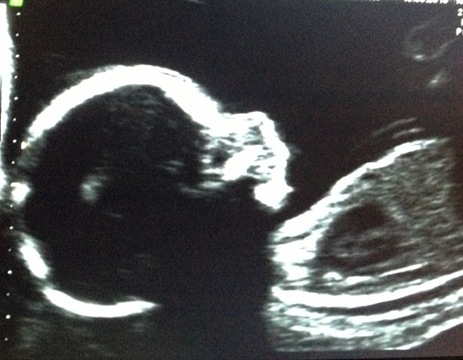

My next little grandbaby, due in September, continues to thrive.